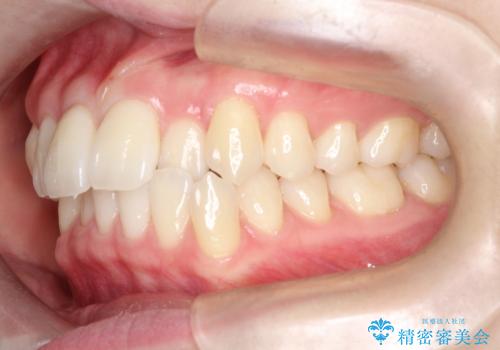

- 左上2の反対咬合(交叉咬合)をインビザラインを用いて治療しました。反対咬合は、歯列の不正咬合の一つであり、上の歯が下の歯よりも内側に位置する状態です。反対咬合は咀嚼や発音に影響を与えることがあります。

左上2の反対咬合をインビザラインで治療する際に、IPR(Interproximal Reduction)を行いました。 IPRとは、隣接する歯の間のエナメル質をわずかに削る手法で、歯の幅を減少させることによって歯列を整える技術です。